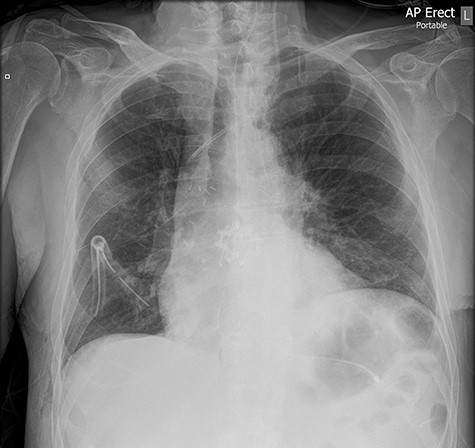

The left basal chest drain was removed without incident on Day 5. However, the nurse encountered resistance during attempted removal of the right basal chest drain. The intern was subsequently notified. Resistance was also encountered by the intern during a further attempt to remove the chest drain. A chest X-ray performed earlier in the day was reviewed (Fig. 2). It demonstrated kinking of the drain around a rib. The intern altered the direction of traction in order to account for the kinking but, during gentle traction, the chest drain fractured at the 14-cm mark (Fig. 3) and became retained within the right hemithorax (Fig. 4). The thoracostomy wound was closed and senior help was immediately sought.

Chest X-ray demonstrating kinking of the chest tube around a rib on the right side.